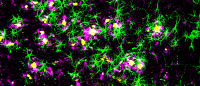

Cleaning the brain. A green tracer fluid flows through the brain's glymphatic system, a recently discovered waste disposal system. The system moves waste along the outer edges of the brain's blood vessels (red). Images provided by Kai Chen.

“It looks like the cells have enough of these AQP4 channels, but they’re not in the right locations in the cells,” Yang says. Normally, the channels are located at the endfeet of the astrocytes, star-shaped brain cells that control the glymphatic system. But in mice and people with Alzheimer’s, the researchers found the channels distributed all around the astrocytes, which hindered waste removal from the cells.